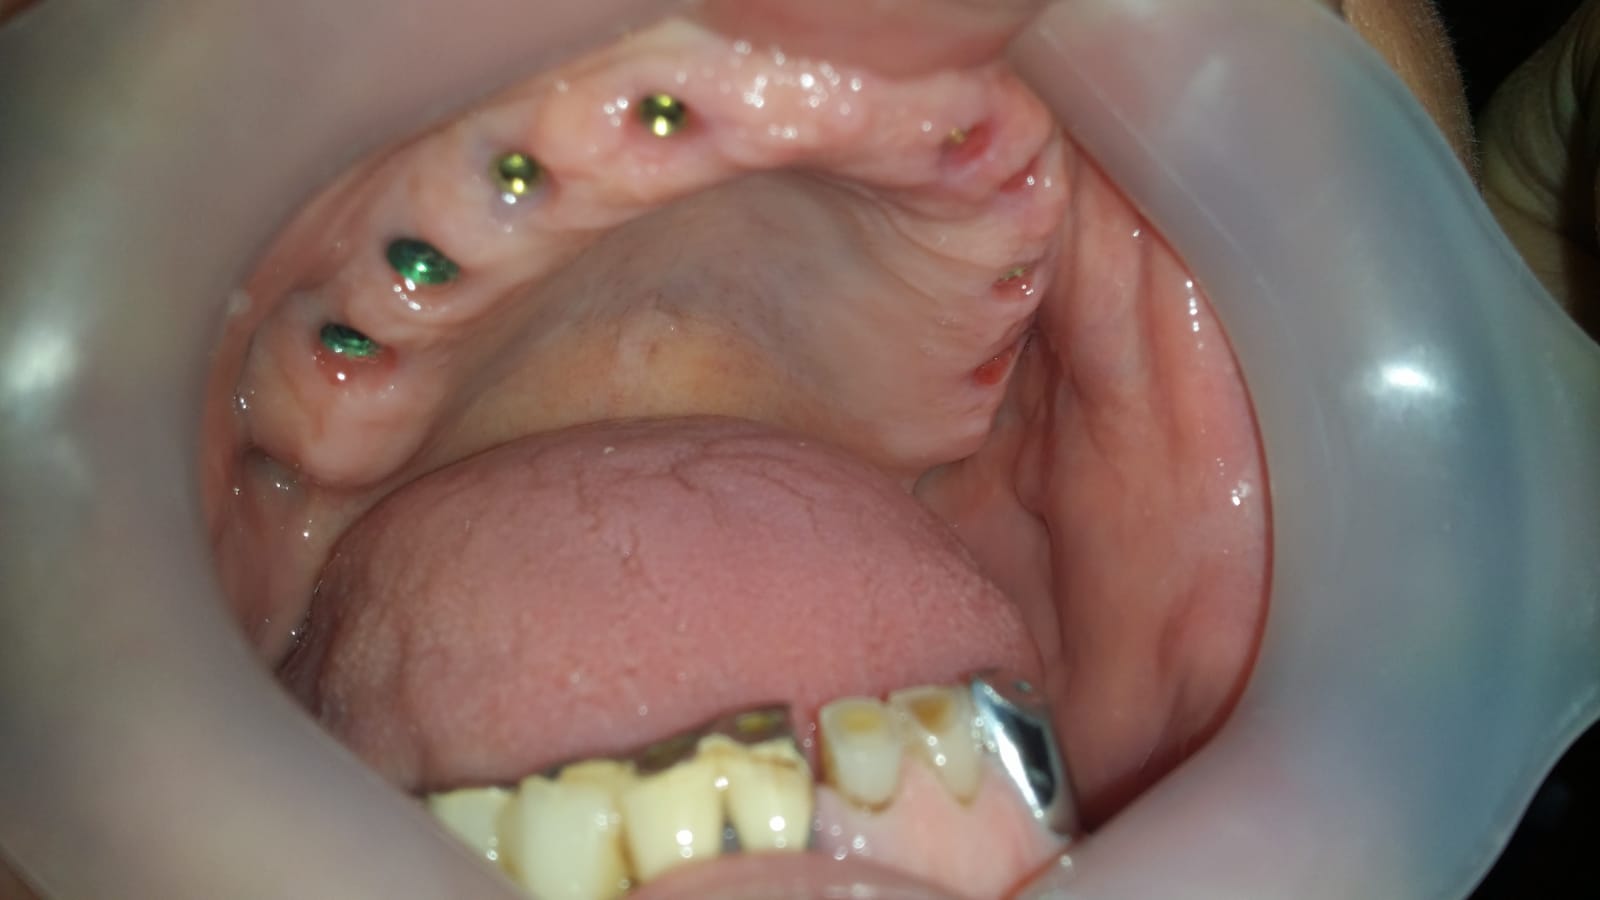

Pacientului i se insereaza implanturile dentare pe care se fixeaza lucrarea dentara (presupune extractie,implantare si realizarea lucrarii fixe imediat)

La finalul sedintei ,pacientul paraseste clinica cu implanturi si dinti ficsi, fiind capabil sa se reintoarca imediat la viata sociala

Punte realizată pe 4 implanturi dentare la mandibula și 6 implanturi la maxilar All in One